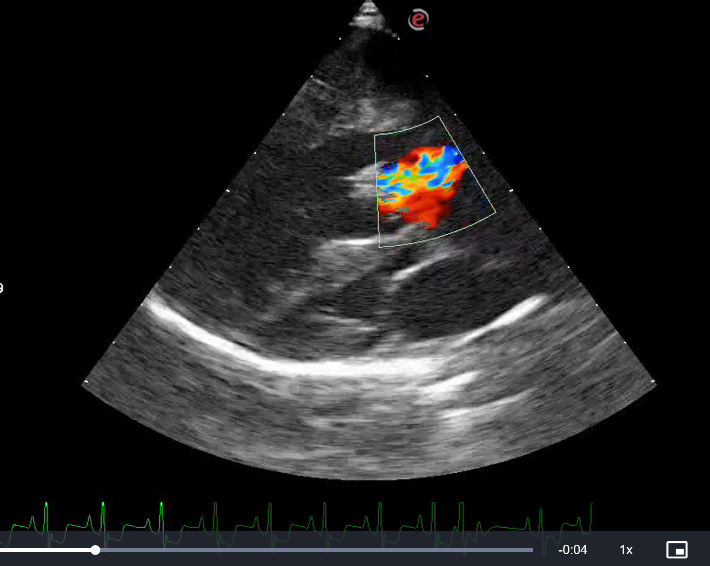

Images #1 and #2. Left - right parasternal long-axis 4-chamber view showing the right ventricle (RV) and atrium (RA) enlargement compared to the LV and LA, and hypertrophy of the right ventricular free wall (asterisk). Right - color flow Doppler showing the significant tricuspid valve regurgitation.

Image #4. Right parasternal short-axis view showing the pulmonic valve thickening (arrow), color flow Doppler of the pulmonic regurgitation and proximal narrowing of the pulmonary artery (PA).